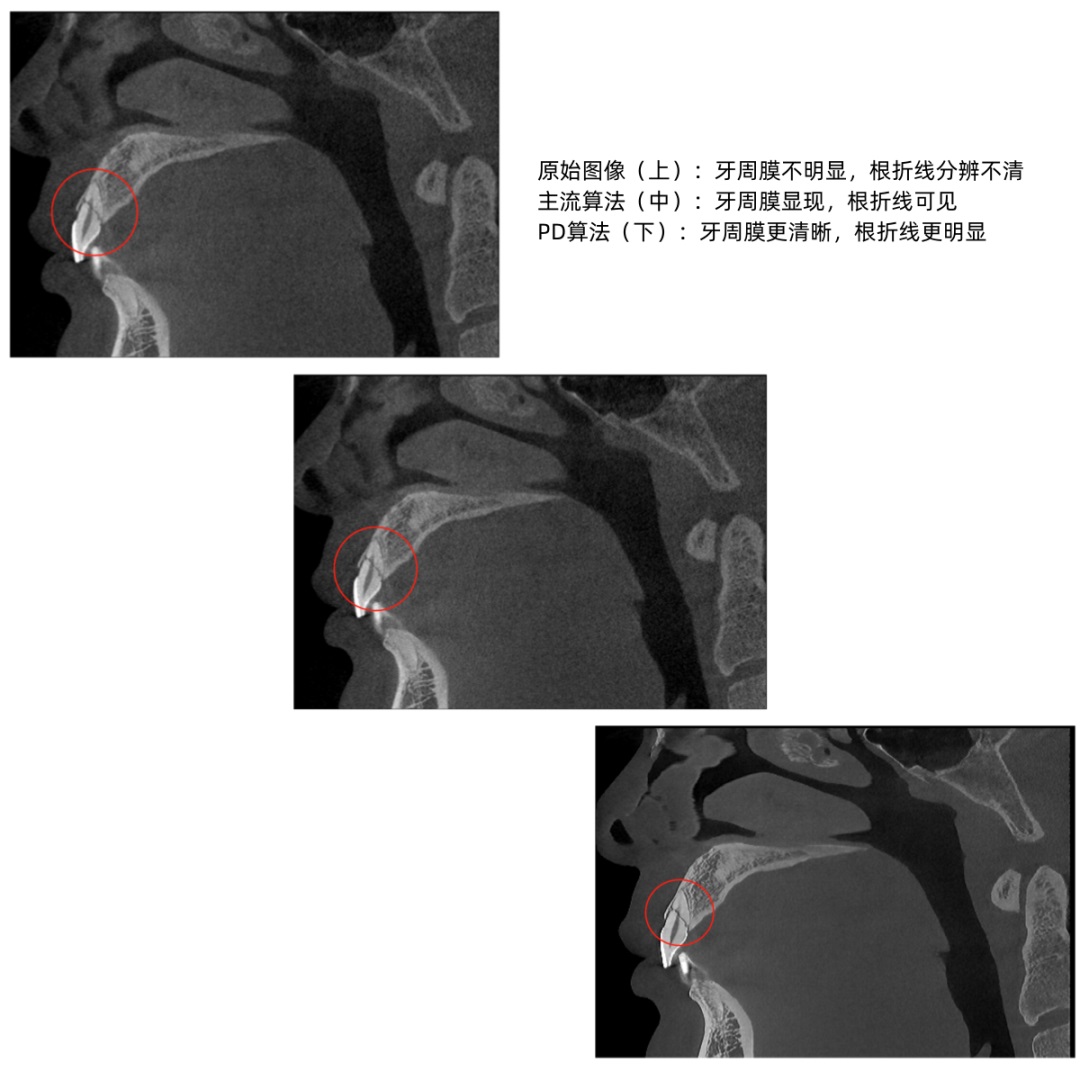

Providing high-quality images for clinical diagnosis and treatment is the core value of dental CBCT. Since the introduction of the first domestically produced dental CBCT in 2012, Meyer has been continuously striving for innovation in core technology. Currently, to achieve imaging effects of "low radiation, low noise, and realistic image texture," the company has introduced the new "PD" technology, namely Pure-Detail Image Enhancement Technology, to empower users to achieve more precise and safe clinical diagnosis and treatment.

Currently, in pursuit of visual "quality perception," some dental CBCT brands may highlight image clarity by modifying contrast and sharpening, but this can distort and lose detailed information in the image, similar to the excessive smoothing and beautification effects seen in photo editing software. This, in turn, affects the accuracy of the doctor's diagnosis.

Meyer adheres to the core of diagnostic and treatment needs, deeply integrating technological innovation with it, and providing clinical services with real and reliable images. The newly introduced "PD" technology can intelligently adjust various parameters through adaptive capability and, based on a large number of shooting results for verification, give the images a "natural texture" effect. It effectively addresses the challenge of noise reduction obscuring minor lesions and provides clearer restoration of bone and soft tissue structure details.

▲From left to right: Original Image, Mainstream Algorithm, "PD" Technology

▲Advantages of "PD" Technology: Deep Restoration of Image Details